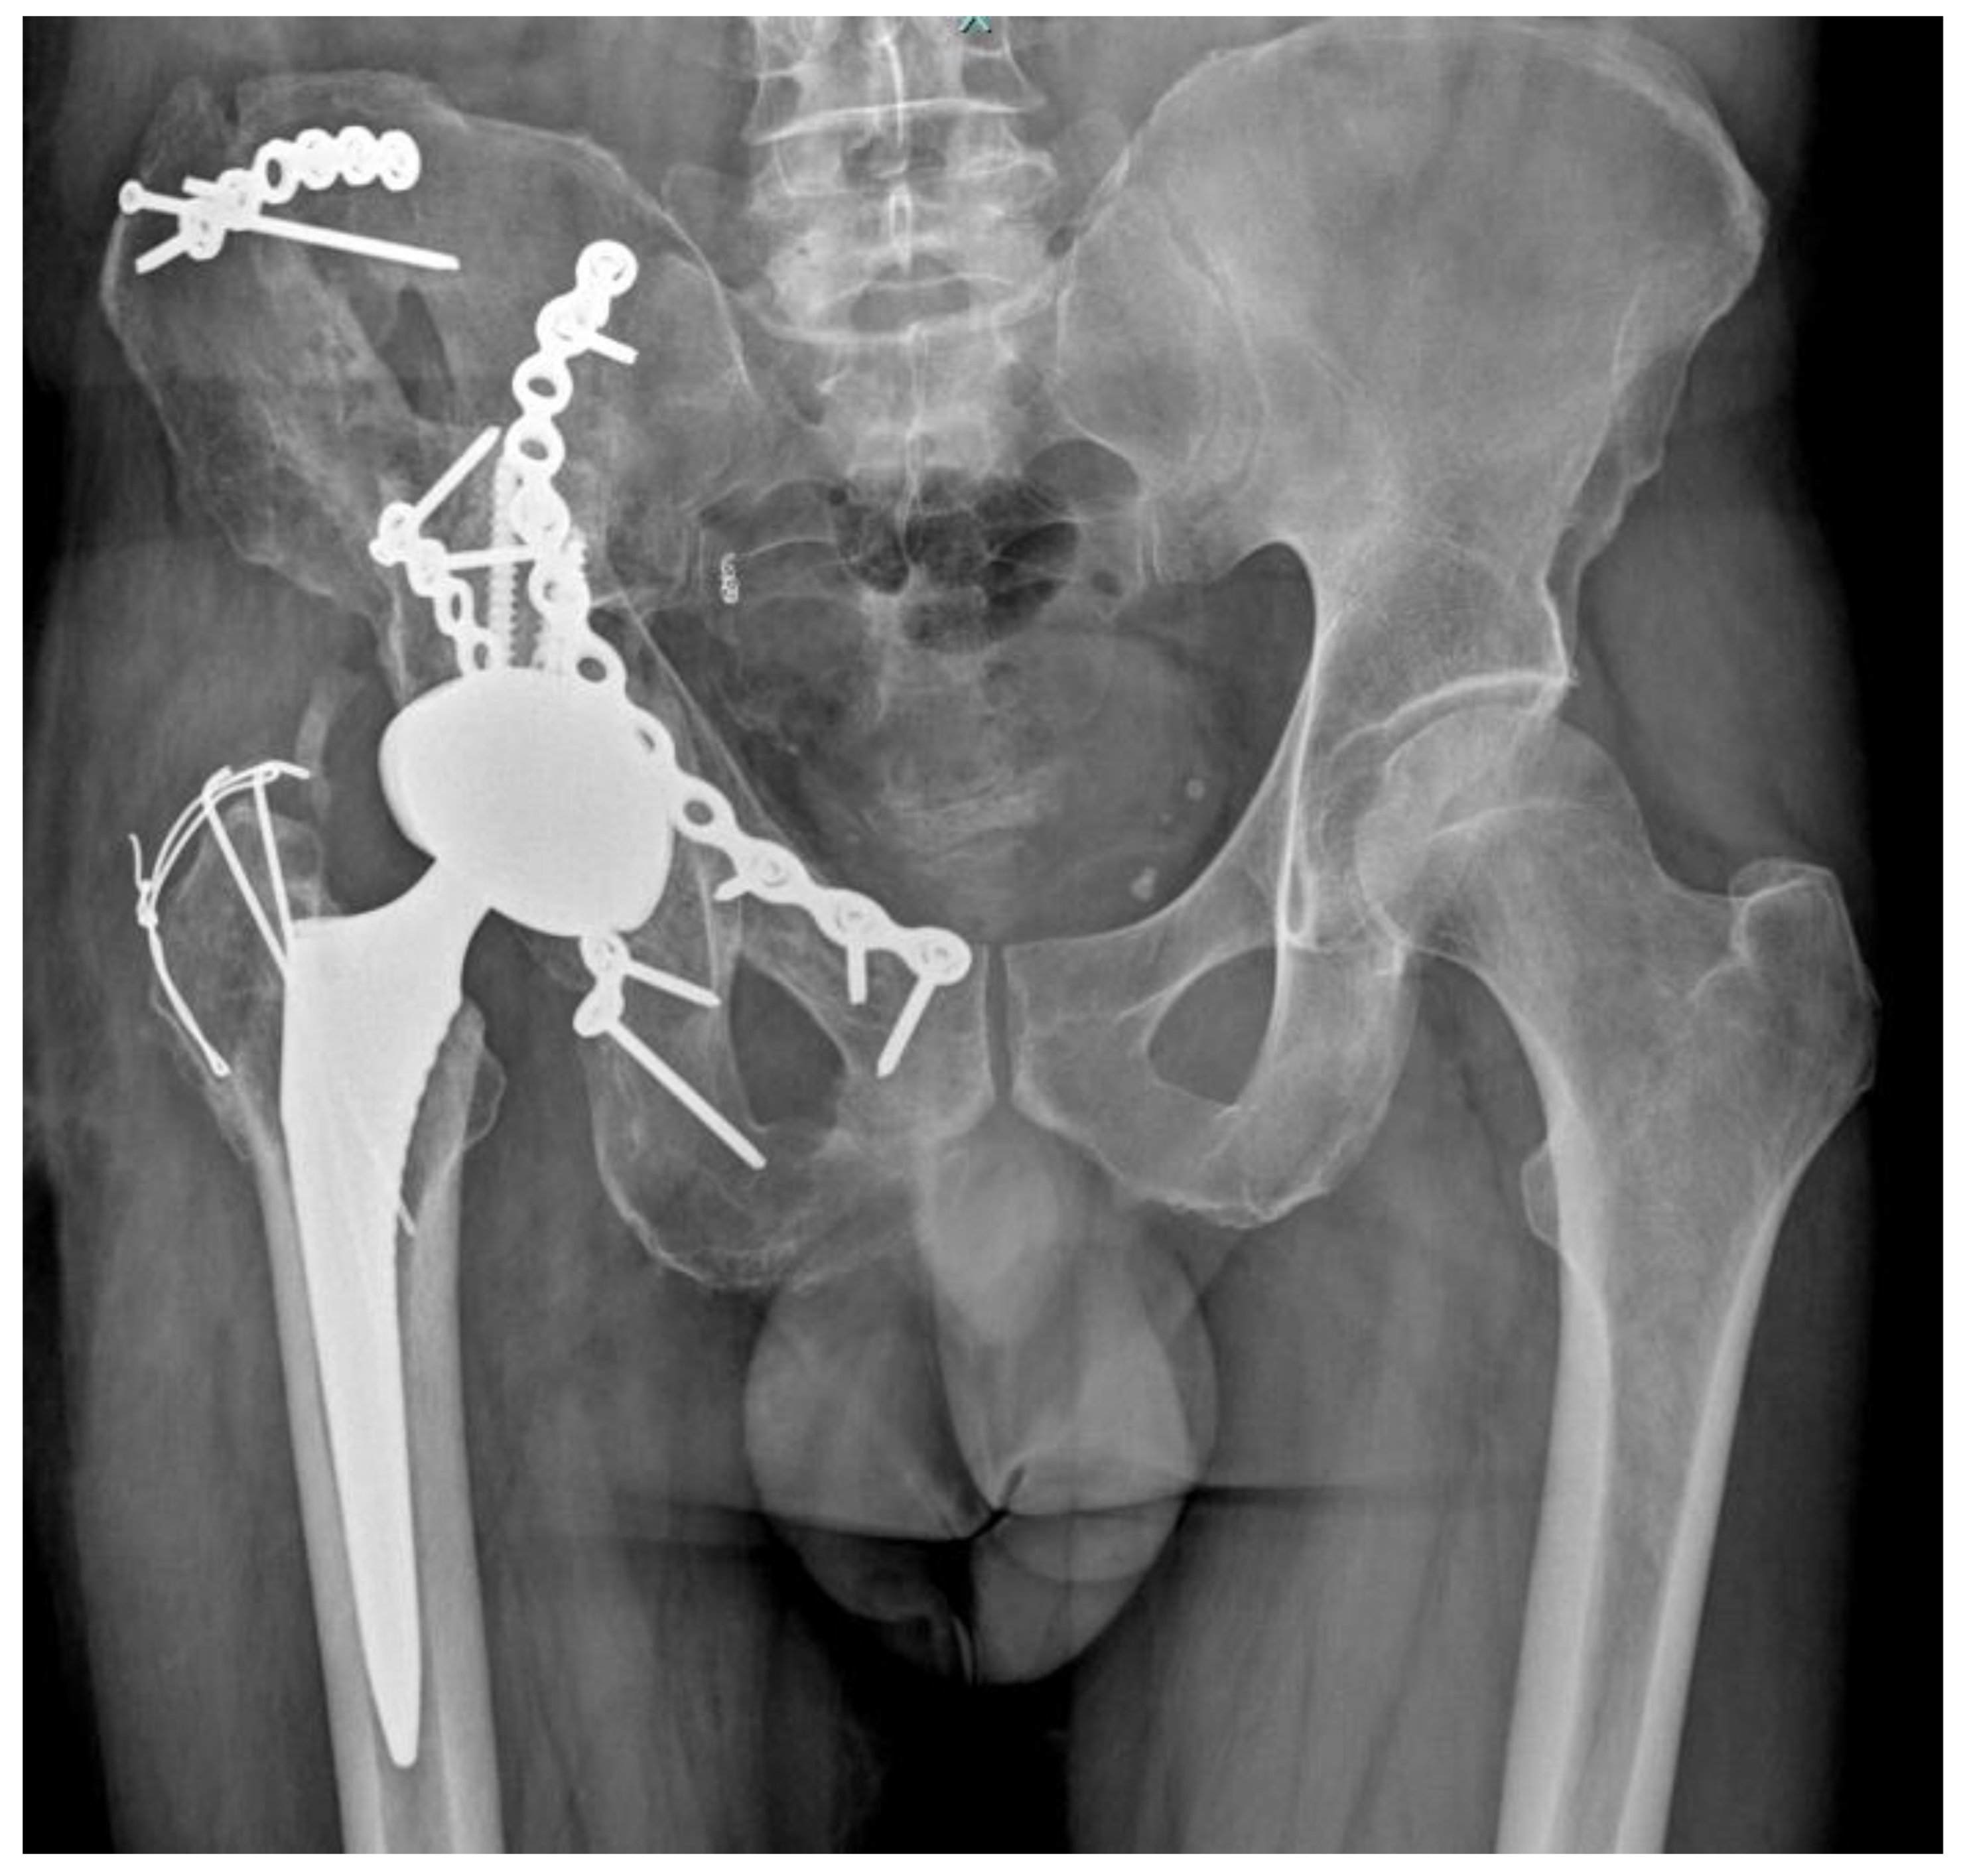

2. Case Report